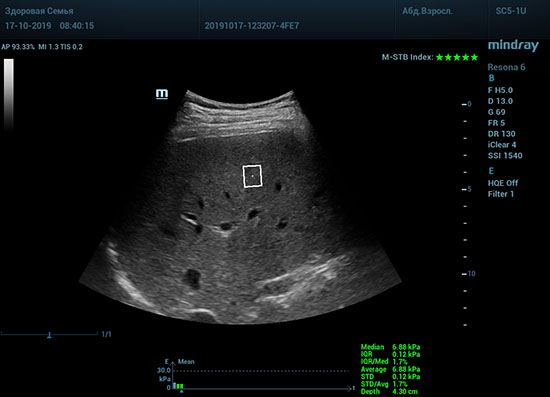

Определение плотности печени. Не ошибся ли оператор при измерении эластических свойств печени? Для оценки критериев качества предусмотрен индекс MBT, который покажет насколько «твердой» была рука оператора и двигалась ли печень. При MBT 5* рука тверда и показатели достоверны. Для оценки качества результатов используется IQR индекс, отображающий колебания показателей в точке измерения при расчете медианы. Показатели при IQR <30% считаются приемлемыми. Техника сканирования через межреберные промежутки требует размещение окна интереса на несколько сантиметром ниже капсулы, для исключения эффекта реверберации. Установка ROI на паренхиму без захвата сосудов, для исключения погрешностей измерения.